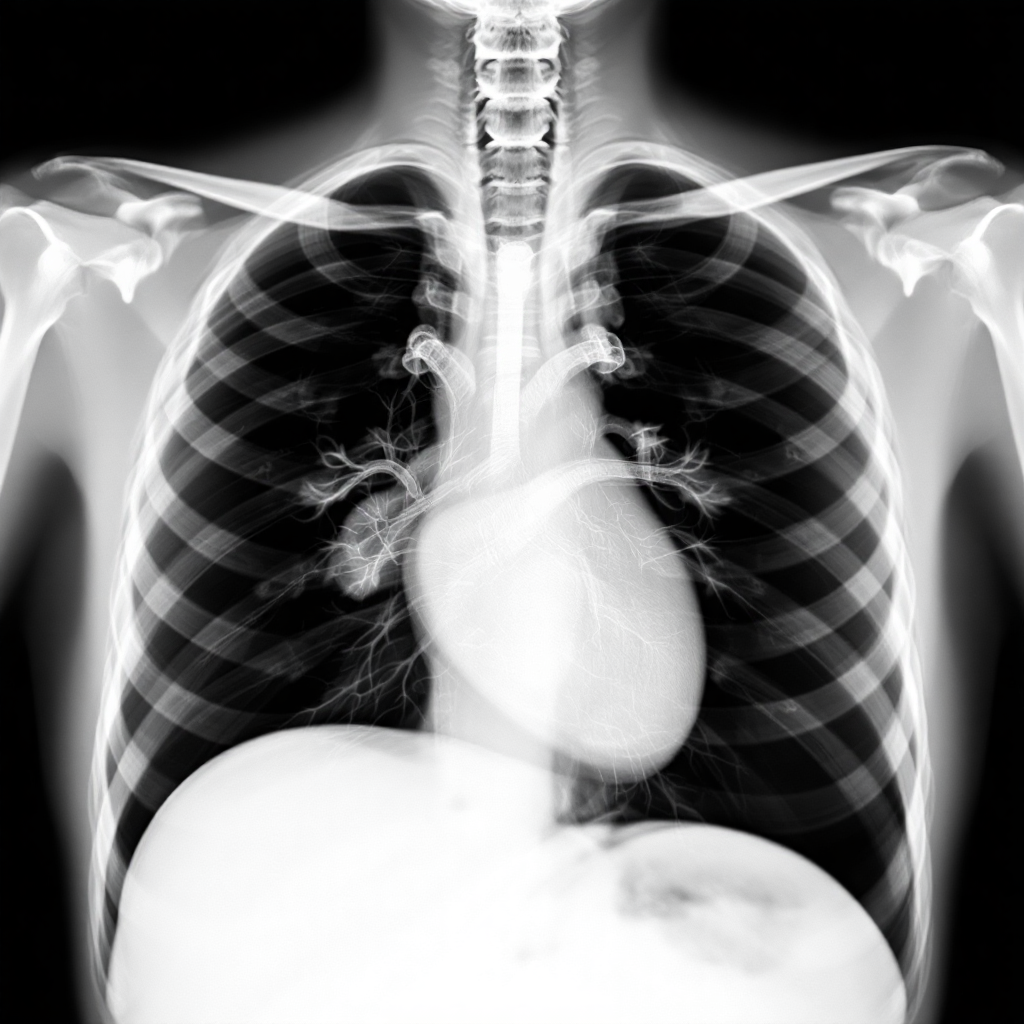

흉부 X-ray PA 촬영은 방사선을 이용해 가슴 안쪽의 구조물들을 영상으로 만드는 검사예요. X-ray는 우리 몸을 투과하면서 각 조직의 밀도에 따라 다르게 흡수되는 특성을 가지고 있어요. 뼈처럼 밀도가 높은 조직은 X-ray를 많이 흡수해서 흰색으로 나타나고, 공기가 찬 폐는 검은색으로 보이게 되죠. 이런 원리를 통해 의사들은 폐렴, 폐결핵, 폐암, 심장 비대 등 다양한 질환을 진단할 수 있어요.

PA 촬영법이 가장 표준적인 방법으로 사용되는 이유는 심장이 필름에 가까이 위치하게 되어 심장의 실제 크기에 가깝게 촬영되기 때문이에요. 만약 AP(Anterior-Posterior) 방식으로 촬영하면 심장이 확대되어 보일 수 있어서 정확한 진단에 어려움이 있을 수 있답니다. 그래서 대부분의 병원에서는 환자가 서서 가슴을 필름에 대고 촬영하는 PA 방식을 선호해요.